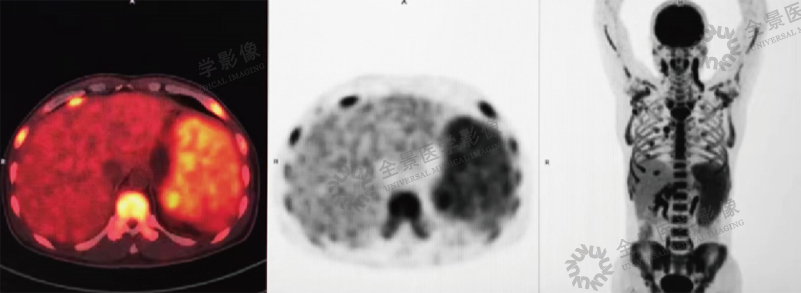

案例:青年男性,因发热伴脾肿大1个月,2016年1月来本中心行PET/CT检查,发现脾脏明显肿大、肝门区淋巴结肿大及全身骨髓腔广泛摄取,

均伴FDG明显高摄取。

结论:诊断为淋巴瘤。后临床确诊为弥漫大B细胞性淋巴瘤。

治疗前: